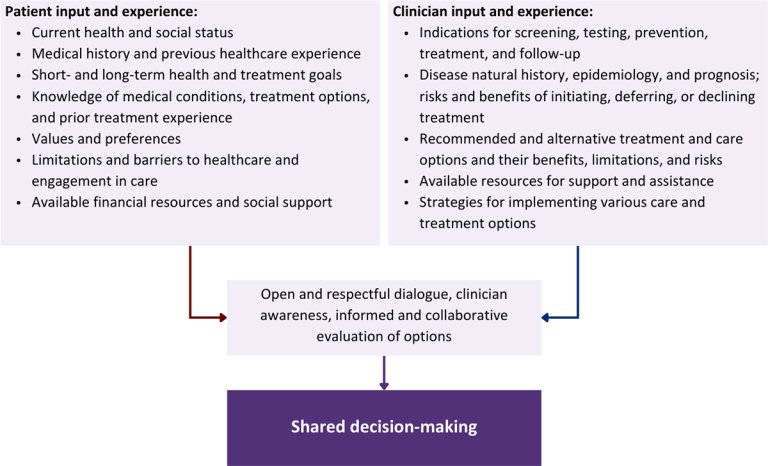

Rationale

Throughout its guidelines, the New York State Department of Health (NYSDOH) AIDS Institute (AI) Clinical Guidelines Program recommends “shared decision-making,” an individualized process central to patient-centered care. With shared decision-making, clinicians and patients engage in meaningful dialogue to arrive at an informed, collaborative decision about a patient’s health, care, and treatment planning. The approach to shared decision-making described here applies to recommendations included in all program guidelines. The included elements are drawn from a comprehensive review of multiple sources and similar attempts to define shared decision-making, including the Institute of Medicine’s original description [Institute of Medicine 2001]. For more information, a variety of informative resources and suggested readings are included at the end of the discussion.

Approach

Collaborative care: Shared decision-making is an approach to healthcare delivery that respects a patient’s autonomy in responding to a clinician’s recommendations and facilitates dynamic, personalized, and collaborative care. Through this process, a clinician engages a patient in an open and respectful dialogue to elicit the patient’s knowledge, experience, healthcare goals, daily routine, lifestyle, support system, cultural and personal identity, and attitudes toward behavior, treatment, and risk. With this information and the clinician’s clinical expertise, the patient and clinician can collaborate to identify, evaluate, and choose from among available healthcare options [Coulter and Collins 2011]. This process emphasizes the importance of a patient’s values, preferences, needs, social context, and lived experience in evaluating the known benefits, risks, and limitations of a clinician’s recommendations for screening, prevention, treatment, and follow-up. As a result, shared decision-making also respects a patient’s autonomy, agency, and capacity in defining and managing their healthcare goals. Building a clinician-patient relationship rooted in shared decision-making can help clinicians engage in productive discussions with patients whose decisions may not align with optimal health outcomes. Fostering open and honest dialogue to understand a patient’s motivations while suspending judgment to reduce harm and explore alternatives is particularly vital when a patient chooses to engage in practices that may exacerbate or complicate health conditions [Halperin, et al. 2007].

Options: Implicit in the shared decision-making process is the recognition that the “right” healthcare decisions are those made by informed patients and clinicians working toward patient-centered and defined healthcare goals. When multiple options are available, shared decision-making encourages thoughtful discussion of the potential benefits and potential harms of all options, which may include doing nothing or waiting. This approach also acknowledges that efficacy may not be the most important factor in a patient’s preferences and choices [Sewell, et al. 2021].

Clinician awareness: The collaborative process of shared decision-making is enhanced by a clinician’s ability to demonstrate empathic interest in the patient, avoid stigmatizing language, employ cultural humility, recognize systemic barriers to equitable outcomes, and practice strategies of self-awareness and mitigation against implicit personal biases [Parish, et al. 2019].

Caveats: It is important for clinicians to recognize and be sensitive to the inherent power and influence they maintain throughout their interactions with patients. A clinician’s identity and community affiliations may influence their ability to navigate the shared decision-making process and develop a therapeutic alliance with the patient and may affect the treatment plan [KFF 2023; Greenwood, et al. 2020]. Furthermore, institutional policy and regional legislation, such as requirements for parental consent for gender-affirming care for transgender people or insurance coverage for sexual health care, may infringe upon a patient’s ability to access preventive- or treatment-related care [Sewell, et al. 2021].

Figure 1: Elements of Shared Decision-Making

Health equity: Adapting a shared decision-making approach that supports diverse populations is necessary to achieve more equitable and inclusive health outcomes [Castaneda-Guarderas, et al. 2016]. For instance, clinicians may need to incorporate cultural- and community-specific considerations into discussions with women, gender-diverse individuals, and young people concerning their sexual behaviors, fertility intentions, and pregnancy or lactation status. Shared decision-making offers an opportunity to build trust among marginalized and disenfranchised communities by validating their symptoms, values, and lived experience. Furthermore, it can allow for improved consistency in patient screening and assessment of prevention options and treatment plans, which can reduce the influence of social constructs and implicit bias [Castaneda-Guarderas, et al. 2016].

Clinician bias has been associated with health disparities and can have profoundly negative effects [FitzGerald and Hurst 2017; Hall, et al. 2015]. It is often challenging for clinicians to recognize and set aside personal biases and to address biases with peers and colleagues. Consciously or unconsciously, negative or stigmatizing assumptions are often made about patient characteristics, such as race, ethnicity, gender, sexual orientation, mental health, and substance use [Avery, et al. 2019; van Boekel, et al. 2013; Livingston, et al. 2012]. With its emphasis on eliciting patient information, a shared decision-making approach encourages clinicians to inquire about patients’ lived experiences rather than making assumptions and to recognize the influence of that experience in healthcare decision-making.